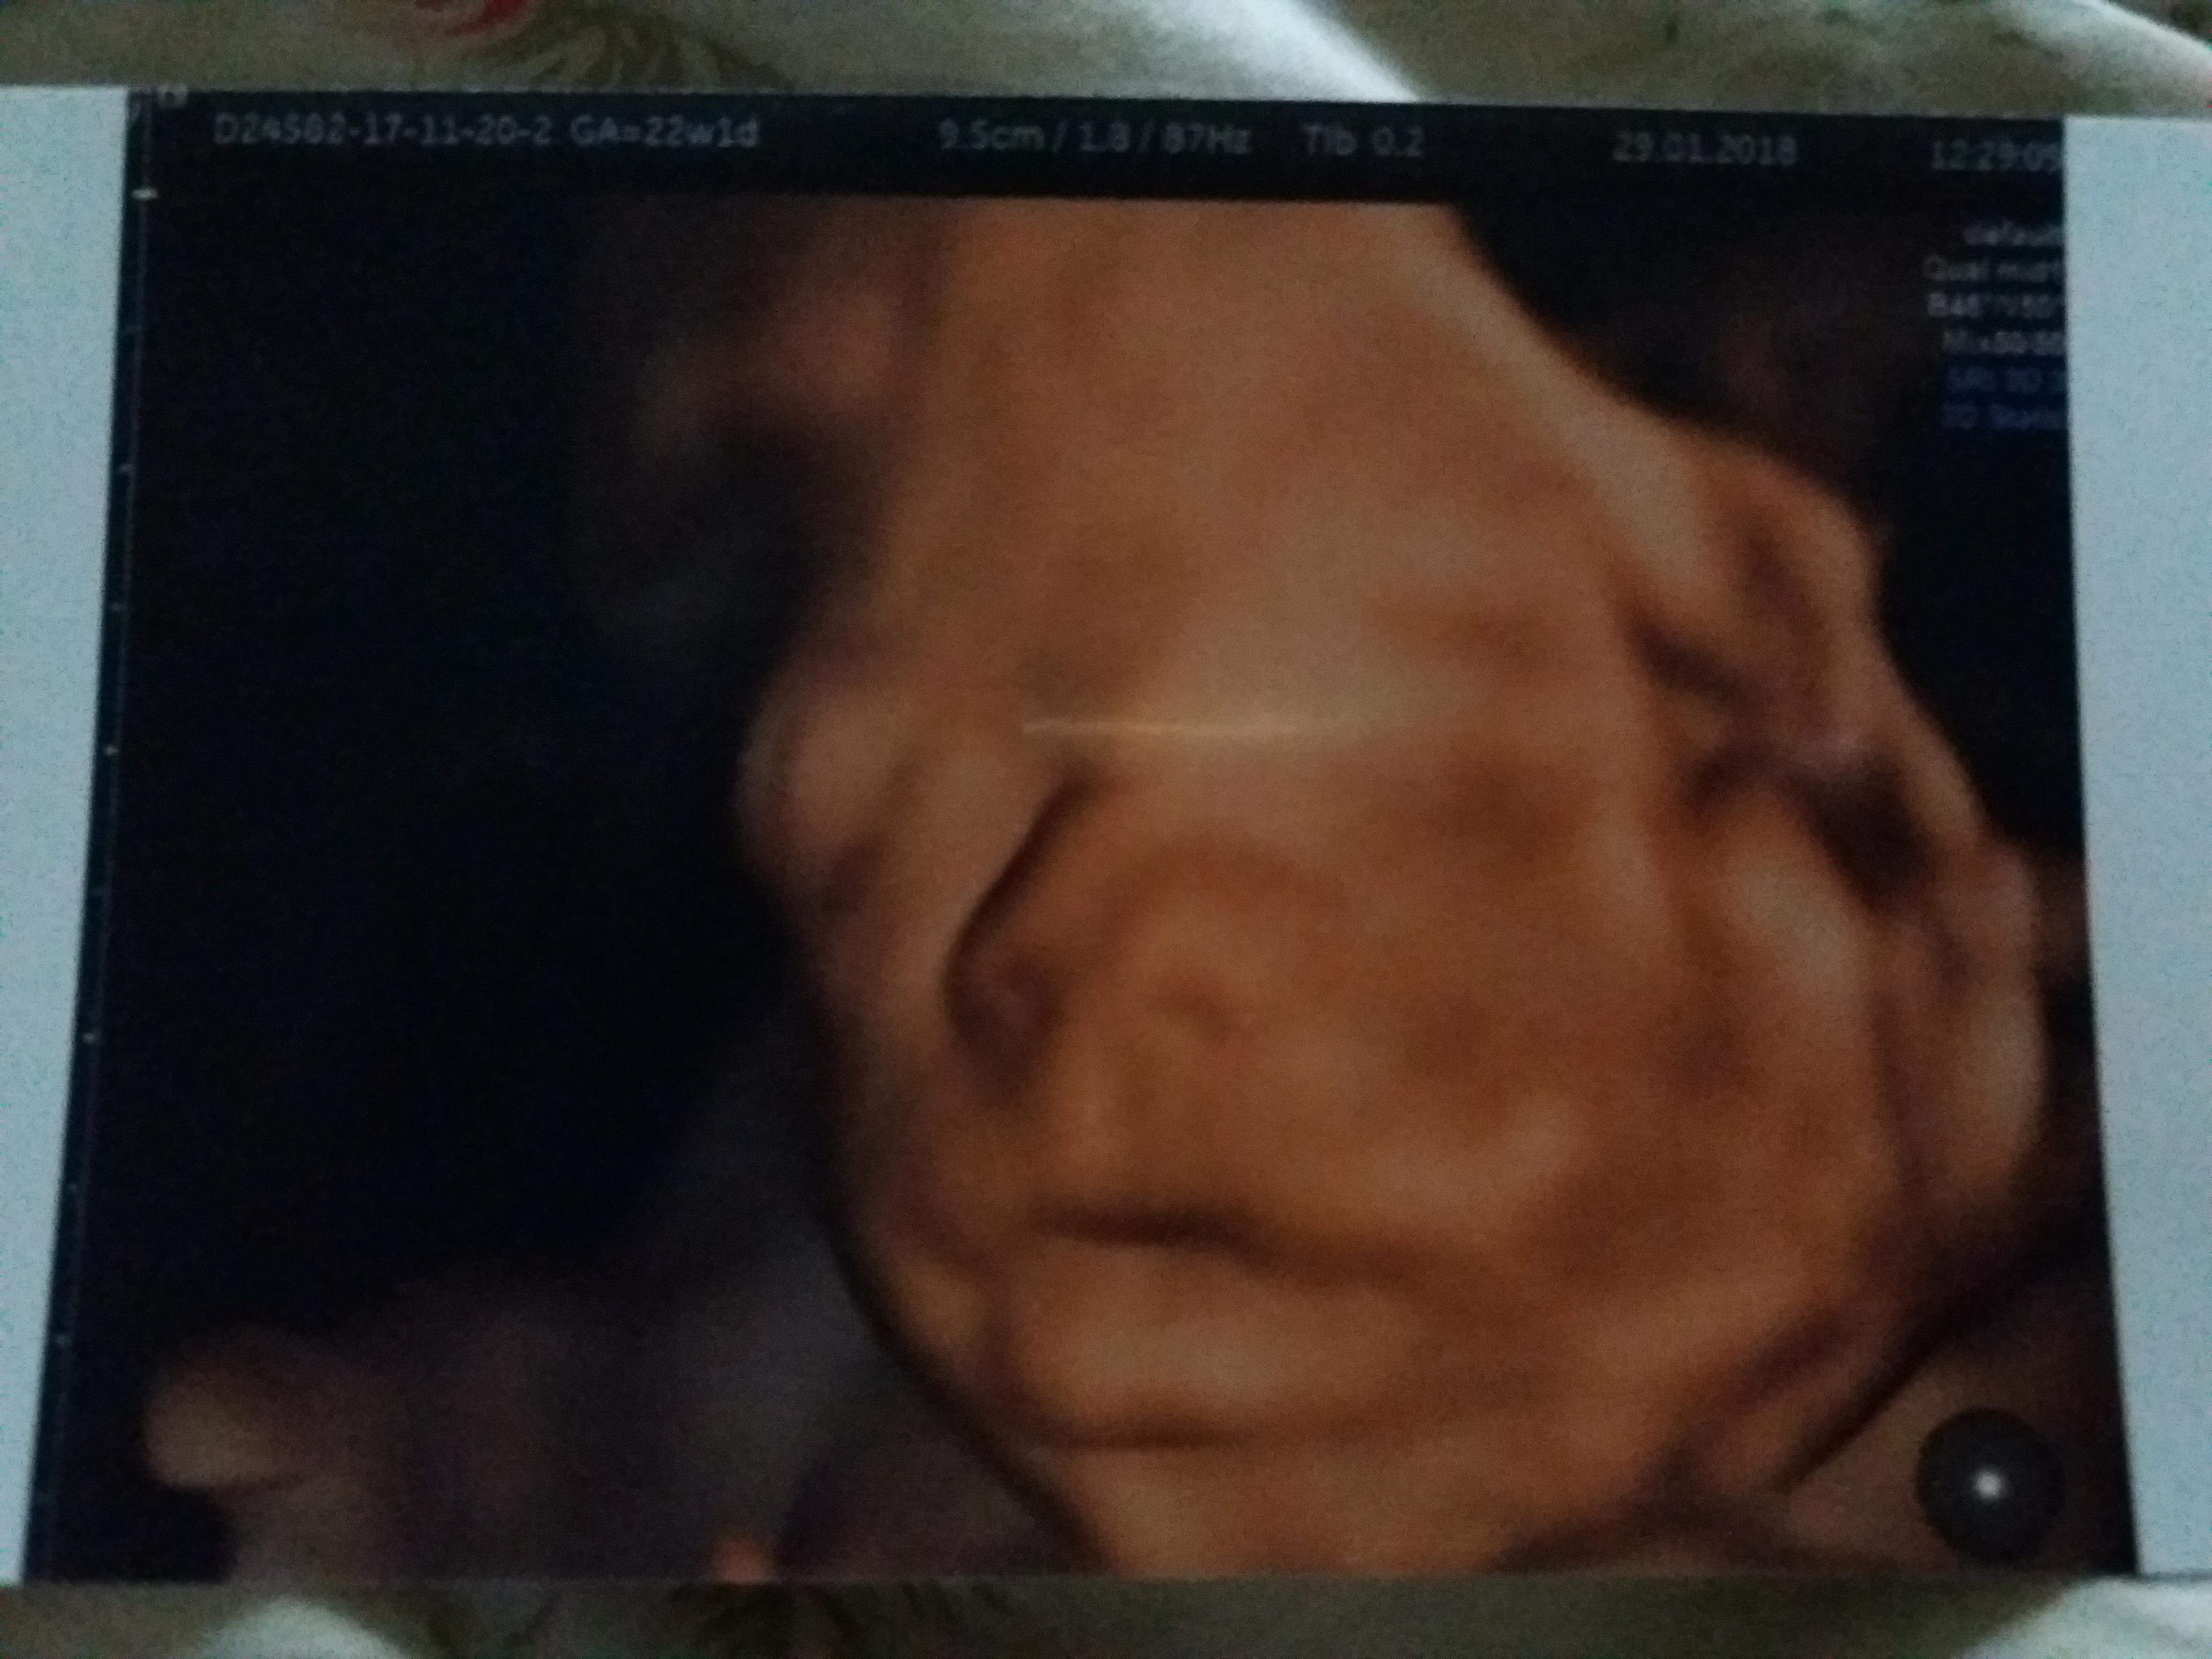

Ja już po polowkowym. Maluszek zdrowiutki. Pięknie rośnie. Obecnie ma 504 g. Moje usg trwało 50 min. Lobuziak nie chciał się obrócić i twarzy pokazać ale wreszcie się udało. Mam piękne zdjęcie i płytę :-)

Załączniki

• received_1805779276163763.jpeg

received_1805779276163763.jpeg

774,7 KB · Wyświetleń: 132